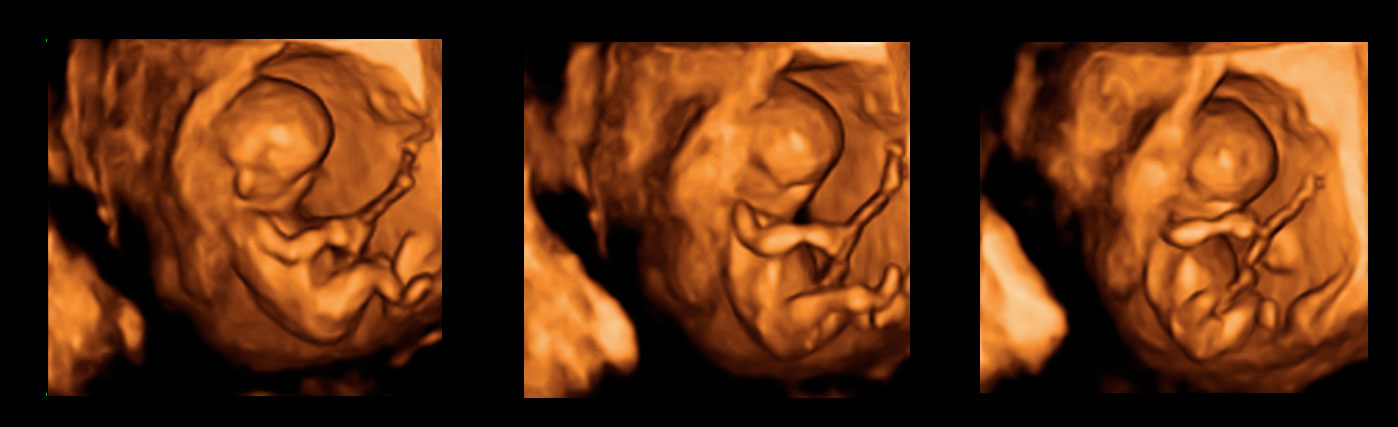

Bebé de 12 semanas de embarazo en una ecografía 3D que muestra un plano rotatorio. El feto está apoyado en las paredes de la cavidad uterina materna. El especial corte de este ultrasonido hace que la imagen parezca una escultura.

Ecografía 3D de un feto de 12 semanas en rotación

Es impresionante ver a este bebé de doce semanas de gestación en este plano rotatorio del útero materno. La sensación de volumen que produce hace que parezca una escultura. El pequeño está apoyado en la paredes uterinas y se tapa la cara con los puños en un gesto fetal característico. Se perfila bien la cara y el tronco del feto, así como el cordón umbilical. Sin embargo, las piernas aparecen más desdibujadas en el vídeo. Este corte de la imagen puede ayudar en el diagnóstico de alguna patología, aunque muchas otras veces se da como recuerdo para la embarazada.